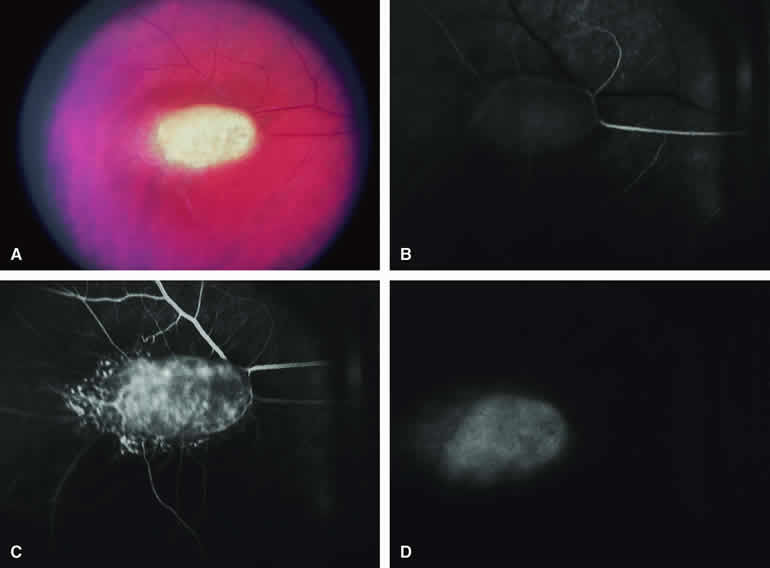

Choroidal Osteoma with Overlying Choroidal Neovascular Membrane

Because choroidal neovascularization is a relatively frequent complication of choroidal osteomas,31 fluorescence angiography may be performed to evaluate the possible presence and extent of this vascular lesion. When present (Fig. 25A), a choroidal neovascular membrane lesion will appear on fluorescein angiography (see Fig. 25B, C, and D) as an abnormal vascular network beneath the retinal pigment epithelium or sensory retina in the early frames of the study and as a smudgy hyperfluorescent lesion showing progressive increase in fluorescence and late staining with leakage in the late frames. If one treats this neovascular membrane by photocoagulation or photodynamic therapy, one can monitor the response of that lesion with a subsequent angiogram of the same type.